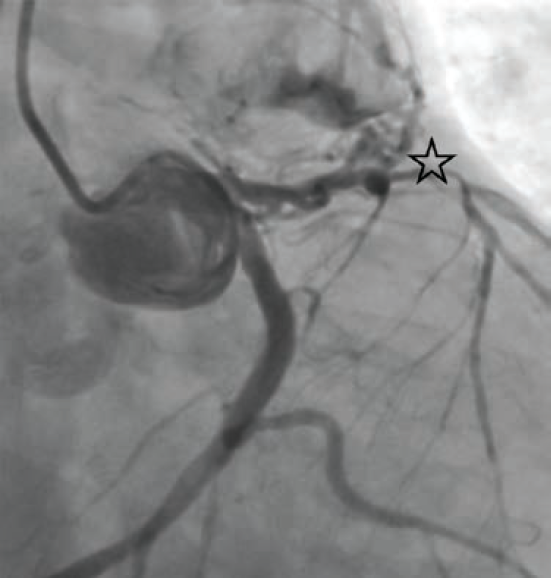

Subsequent left and right heart catheterization revealed a left-dominant coronary circulation, significant obstructive CAD involving the proximal LAD, and a fistula from the LAD to the main pulmonary artery with a pulmonary-to-systemic shunt ratio (Qp/Qs) of 1.3 (Figure 1). Right-sided filling pressures were normal, while pulmonary capillary wedge pressure (PCWP) was moderately elevated. Cardiac index and cardiac output were preserved.